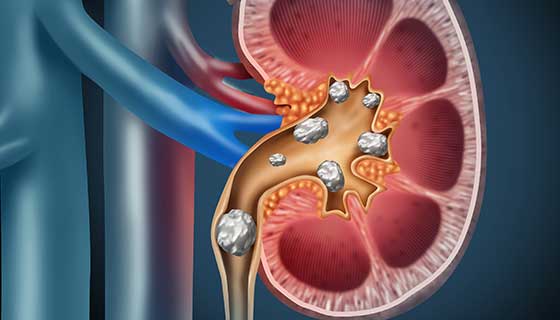

Recurrent renal stones, or kidney stones, are hardened deposits of minerals and salts that form within the kidneys. The formation of these stones is often related to an imbalance in the substances that make up urine. When kidney stones recur, they appear repeatedly, often causing significant discomfort and potential complications. The recurrence of these stones is common, and after the first occurrence, the risk of subsequent stone formation increases, particularly if underlying causes or risk factors are not addressed.

- - Severe Pain: Sudden, sharp pain in the back, side, or groin, often referred to as renal colic, occurs when a stone moves or blocks the urinary tract. - Hematuria: Blood in the urine, which can turn the urine pink, red, or brown. - Frequent Urination: Increased urge to urinate, especially when the stone is near the bladder. - Nausea and Vomiting: Due to intense pain and the body’s response to the obstruction. - Cloudy or Foul-Smelling Urine: Indicative of a possible urinary tract infection accompanying the stone.

- - Infection: Stones can cause urinary tract infections, which may lead to more severe kidney infections. - Obstruction: Stones can block the flow of urine, causing swelling, kidney damage, and acute renal failure. - Kidney Damage: If stones cause repeated blockages, they can lead to chronic kidney disease.